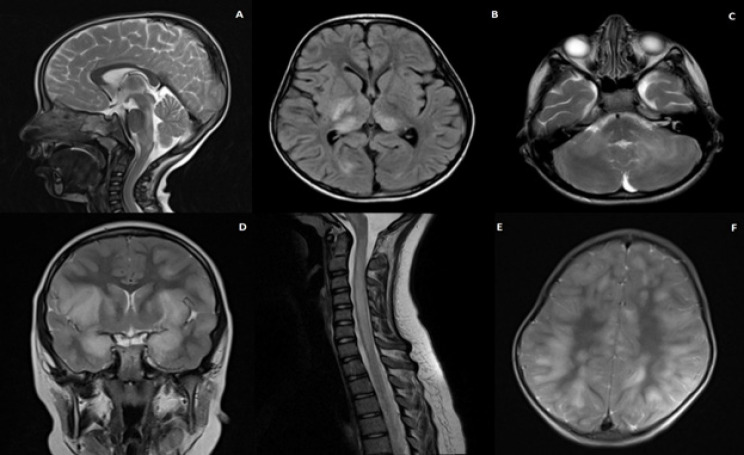

Results: The study reviewed 36 patients, with an average age of 6.08 years and predominantly male (61.1%). Clinical presentations included fever, nausea, vomiting, and seizures, with left facial hemiparesis being more common in girls (P-value = 0.023), while abnormal deep tendon reflexes (DTRs) and right-sided pathologies were more common in older patients (P-value < 0.05). Recent laboratory results have revealed differences between peripheral lymphocytes and polymorphonuclear (PMN) cells. Imaging revealed predominantly bilateral lesions, with older patients more likely to show lesions in the right parietal and occipital lobes (P-value = 0.01 and 0.04). Bilateral parietal lobe lesions were significantly correlated with several laboratory findings across the different subgroups. Multivariate logistic regression revealed that these findings were statistically significant in regards to peripheral PMN and lymphocytes in the age category and cerebrospinal fluid (CSF) protein in the gender category (P-value < 0.05). Additionally, girls, particularly those who were older, had significantly higher involvement of the cervical spine (P-value = 0.04 and 0.02).

Conclusion: This study reveals age and sex-related differences in the clinical presentation and imaging findings of seronegative pediatric ADEM, showcasing the various demographic factors in patient profiles.